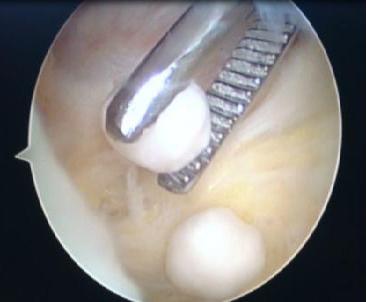

1、膝关节游离体:

游离体

这是我们通过关节镜检查后发现的关节内部的游离体,游离体又叫关节鼠,是指关节内有可移动的软骨或骨软骨碎片。关节内游离体可来自软骨,骨软骨或滑膜,可以是完全游离,也可以还有软组织束带相连。会引起关节绞索等症状。

简单来说,就是走走会突然卡住,有时会伴有疼痛。大多数可以自行恢复,但仍会复发。

这其实是关节镜的最佳适应症,大家可以看到,我们通过检查后如果发现是关节内的游离体,那么,只需要将游离体取出就能解决问题。而光靠X线或核磁有时往往并不能准确判断出游离体或该游离体是否存在卡压的情况。